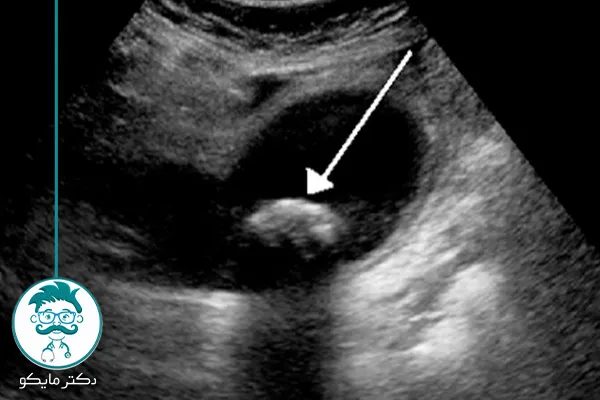

سنگ کیسه صفرا چیست؟

این سنگ ها که باعث یکی از انواع بیماری های گوارشی می شوند، رسوبات سختشدهای هستند که در کیسه صفرا تشکیل میشوند. سنگهای صفراوی از مواد مختلفی تشکیل شدهاند، اما شایعترین نوع آن ها از کلسترول تشکیل شده است. سایر انواع سنگهای صفراوی شامل سنگهای بیلیروبین و سنگهای مخلوط هستند.

اندازه های سنگ کیسه صفرا

سنگهای کیسه صفرا در اندازههای مختلف وجود دارند و گاه بدون علامت هستند.